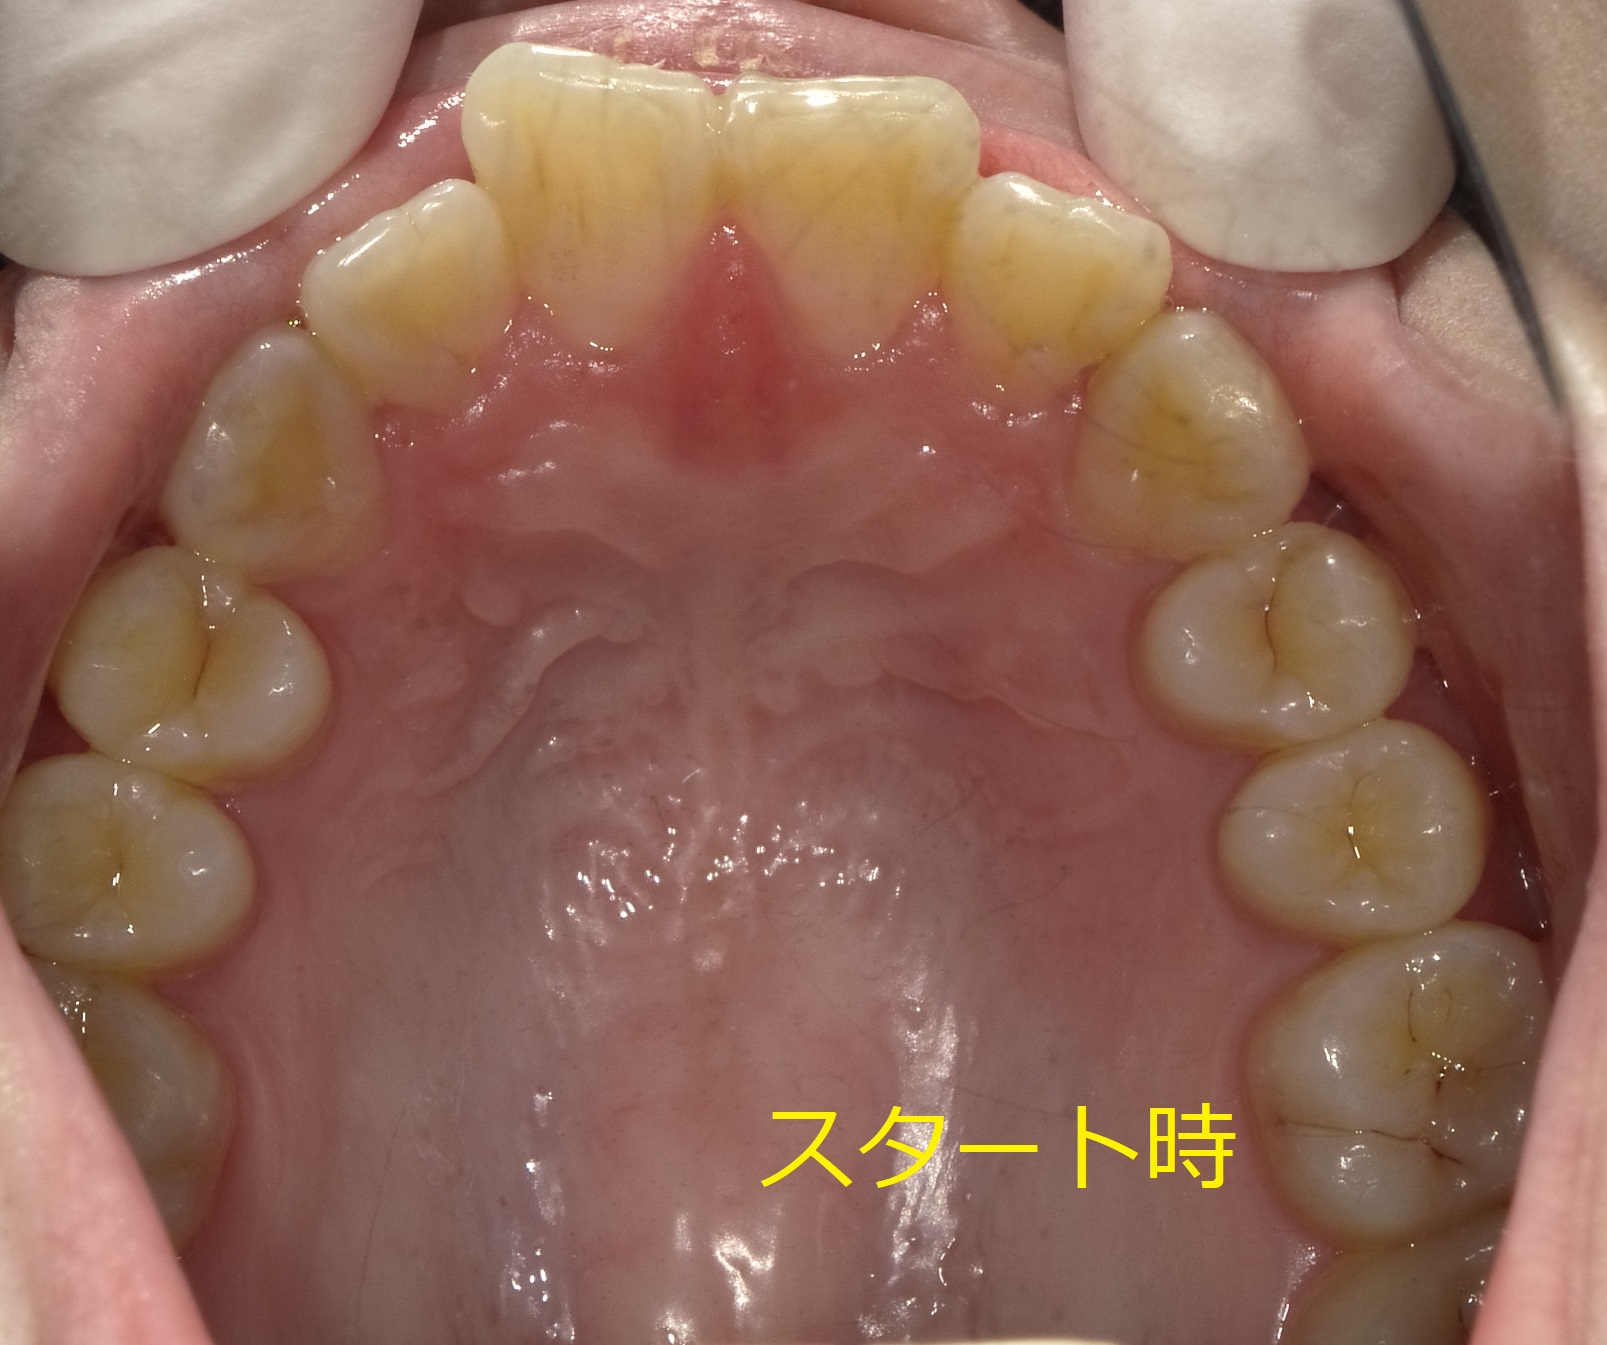

正面からだとさほど並びに問題はなさそうなのですが、下から見ると

このように、「右の前歯が回転しながら前にはみ出している」のが分かります。